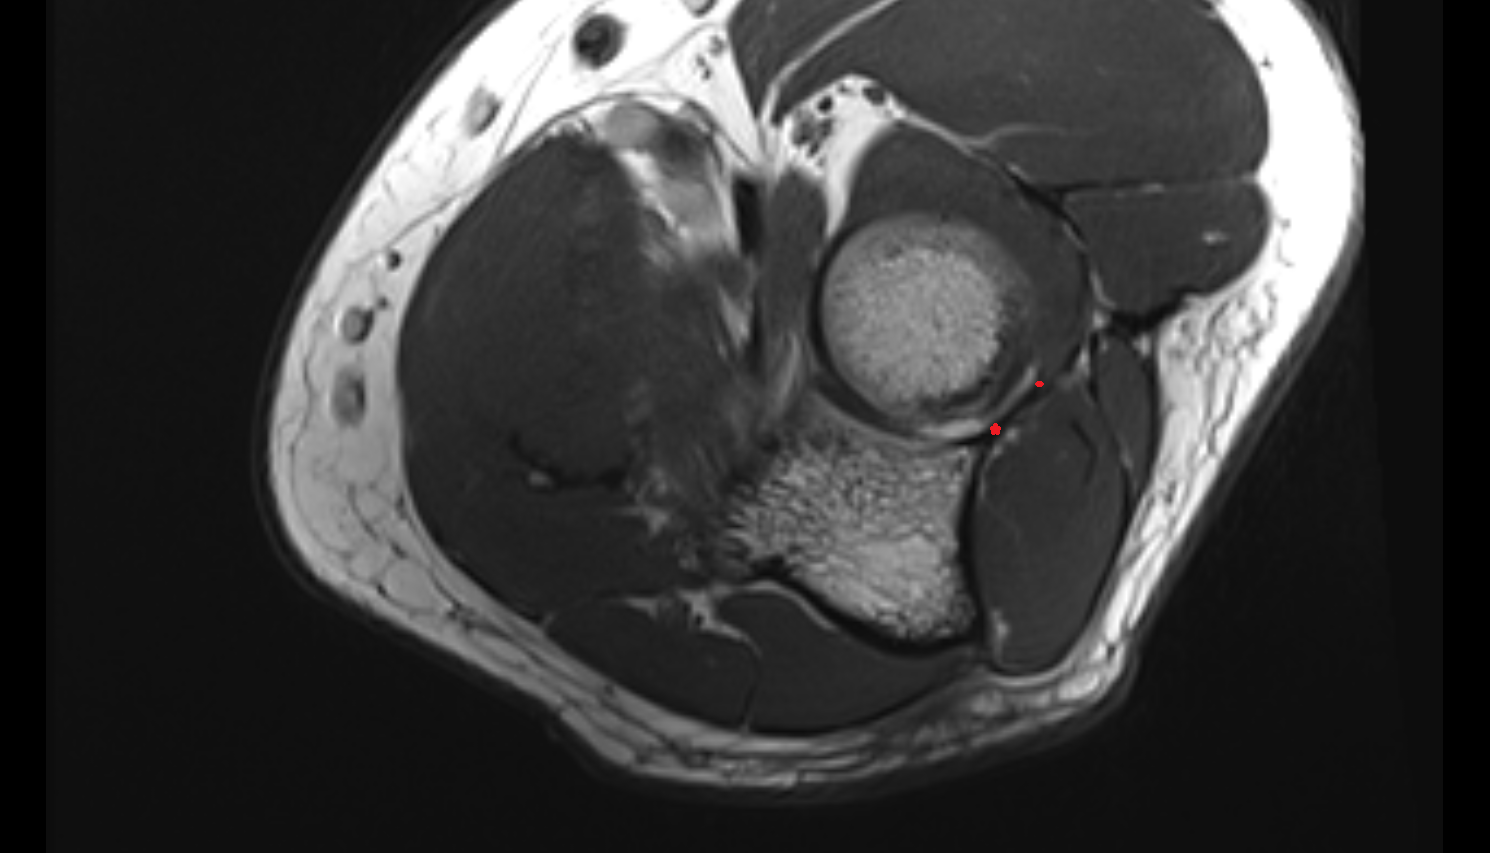

- Knee Joint